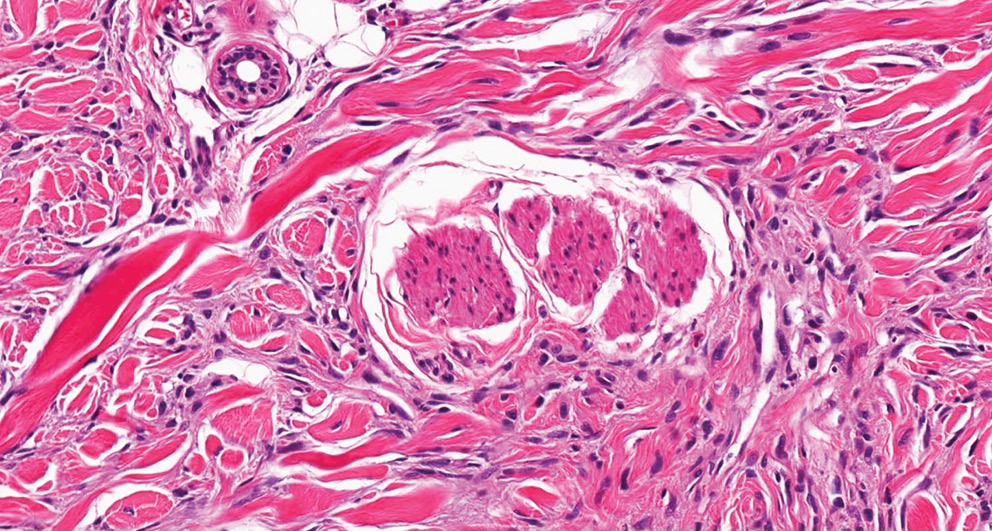

Гистологический анализ показал, что ДМ характеризуется плотной коллагенизированной структурой, низкой клеточной плотностью и гиперхромными атипичными элементами, расположенными в виде дискретных гнезд или линейных структур [6] (рис. 4).

Рис. 4. Десмопластическая меланома (микроскопическое исследование, × 200, окрашивание гематоксилином и эозином). Выраженная распространенная инвазия придатков кожи

Fig. 4. Desmoplastic melanoma (microscopic examination, ×200, H&E staining). Expressed widespread invasion of the skin appendages

У 40% исследованных пациентов была обнаружена нейротропная инвазия, что усложняло дифференциальную диагностику с опухолями периферической нервной системы [7, 8] (рис. 5). Дополнительные гистологические изменения включали лимфоцитарную инфильтрацию и участки с выраженной десмоплазией, что затрудняло диагностику при окрашивании стандартными гистологическими методами [9, 10].

Рис. 5. Десмопластическая меланома (микроскопическое исследование, × 400, окрашивание гематоксилином и эозином). Периневральная инвазия

Fig. 5. Desmoplastic melanoma (microscopic examination, × 400, H&E staining). Perineural invasion